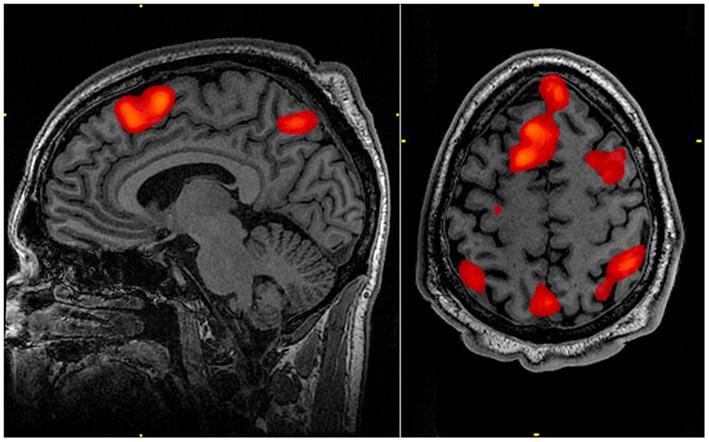

• Biopsychology: The nervous system, the role of neurotransmitters and hormones, localisation of brain function, ways of studying the brain and biological rhythms.